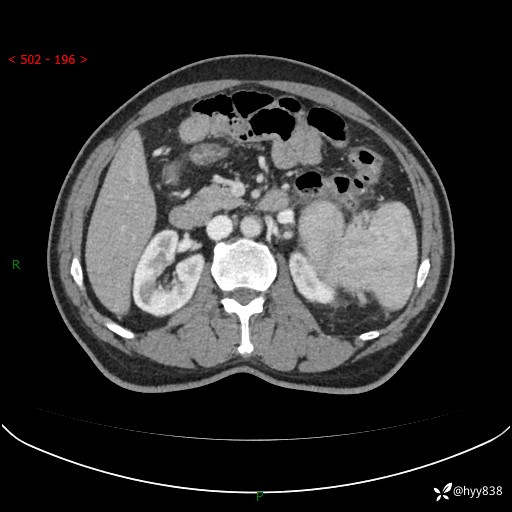

上腹部CT平扫

增强(动脉期+静脉期)